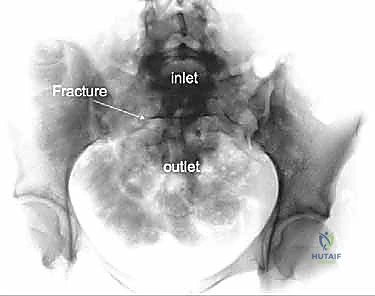

2. الأشعة السينية (X-rays): توفر نظرة أولية سريعة على كسور الحوض (AP, Inlet, and Outlet views).

3. التصوير المقطعي المحوسب (CT Scan): وهو المعيار الذهبي (Gold Standard) لتشخيص كسور الحوض والعجز. يقوم الدكتور هطيف باستخدام تقنية إعادة البناء ثلاثي الأبعاد (3D Reconstruction) لفهم هندسة الكسر بدقة متناهية قبل الدخول إلى غرفة العمليات.